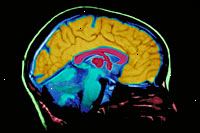

Τι είναι η μαγνητική τομογραφία (MRI);

Μαγνητική τομογραφία (MRI) είναι μία διαγνωστική διαδικασία που χρησιμοποιεί ένα συνδυασμό από ένα μεγάλο μαγνήτη, ραδιοσυχνότητες, και έναν υπολογιστή για να παράγει λεπτομερείς εικόνες των οργάνων και δομών εντός του σώματος.

Το μηχάνημα MRI είναι ένα μεγάλο, κυλινδρικό (σχήμα σωλήνα) μηχανή που δημιουργεί ένα ισχυρό μαγνητικό πεδίο γύρω από τον ασθενή. Αυτό το μαγνητικό πεδίο, μαζί με μια ραδιοσυχνότητα, μεταβάλλει φυσική ευθυγράμμιση Τα άτομα υδρογόνου »στο σώμα. Οι υπολογιστές χρησιμοποιούνται στη συνέχεια για να σχηματίσουν δύο διαστάσεων (2D) εικόνες μιας δομής του σώματος ή όργανο με βάση τη δραστικότητα των ατόμων υδρογόνου. Όψεις διατομής μπορούν να ληφθούν για να αποκαλύψει περαιτέρω λεπτομέρειες. MRI δεν χρησιμοποιεί ιονίζουσα ακτινοβολία, όπως και οι ακτίνες-Χ ή αξονική τομογραφία (αξονική τομογραφία).

Ένα μαγνητικό πεδίο δημιουργείται και οι παλμοί των ραδιοκυμάτων που αποστέλλονται από ένα σαρωτή. Το μαγνητικό πεδίο ευθυγραμμίζει τα πρωτόνια υδρογόνου στο σώμα σας κατά μήκος του ίδιου φορέα. Τα ραδιοκύματα, στη συνέχεια, να χτυπήσει τα σωματίδια από αυτό ευθυγραμμισμένη θέση. Καθώς οι πυρήνες επαναπροσδιορίσουμε πίσω στην κατάλληλη θέση, οι πυρήνες στέλνουν ραδιοσήματα. Αυτά τα σήματα που λαμβάνονται από έναν υπολογιστή που αναλύει και τα μετατρέπει σε μια εικόνα του τμήματος του σώματος που εξετάζεται. Αυτή η εικόνα εμφανίζεται σε μια οθόνη προβολής. Μερικές μηχανές MRI μοιάζουν με στενές σήραγγες, ενώ άλλοι είναι πιο ανοικτή.

Μαγνητικού συντονισμού (MRI) μπορεί να χρησιμοποιηθεί αντί της υπολογιστικής τομογραφίας (CT) σε καταστάσεις όπου τα όργανα ή μαλακού ιστού μελετώνται, γιατί με MRI σάρωση οστά δεν επισκιάζει τις εικόνες των οργάνων και των μαλακών ιστών, όπως κάνει αξονική τομογραφία.